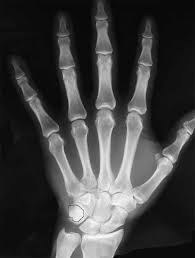

Alpha particles and beta particles are example of particulate radiation while cathode rays are beams of electrons in a partially evacuated glass tube with a potential difference between an. Our online radiology trivia quizzes can be adapted to suit your requirements for taking some of the top radiology quizzes. First, you need to identify the fractures inside the body. May 21, 2018 · radiology questions and answers (q&a) what is an example of particulate radiation? Dec 05, 2017 · more radiology quizzes oral radiology examination practice test! This quiz will test the dental student's understanding and knowledge of radiation physics and the fundamentals of radiographic interpretation. Apr 06, 2021 · a comprehensive database of more than 14 radiology quizzes online, test your knowledge with radiology quiz questions. Next, you need to diagnose the underlying condition.

First, you need to identify the fractures inside the body.